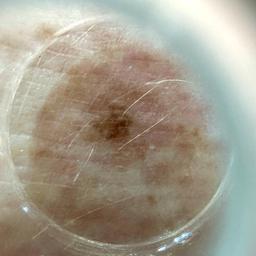

ISIC_3060871

2487 x 2487

diagnosis_1 Benign

diagnosis_confirm_type single image expert consensus

image_type dermoscopic